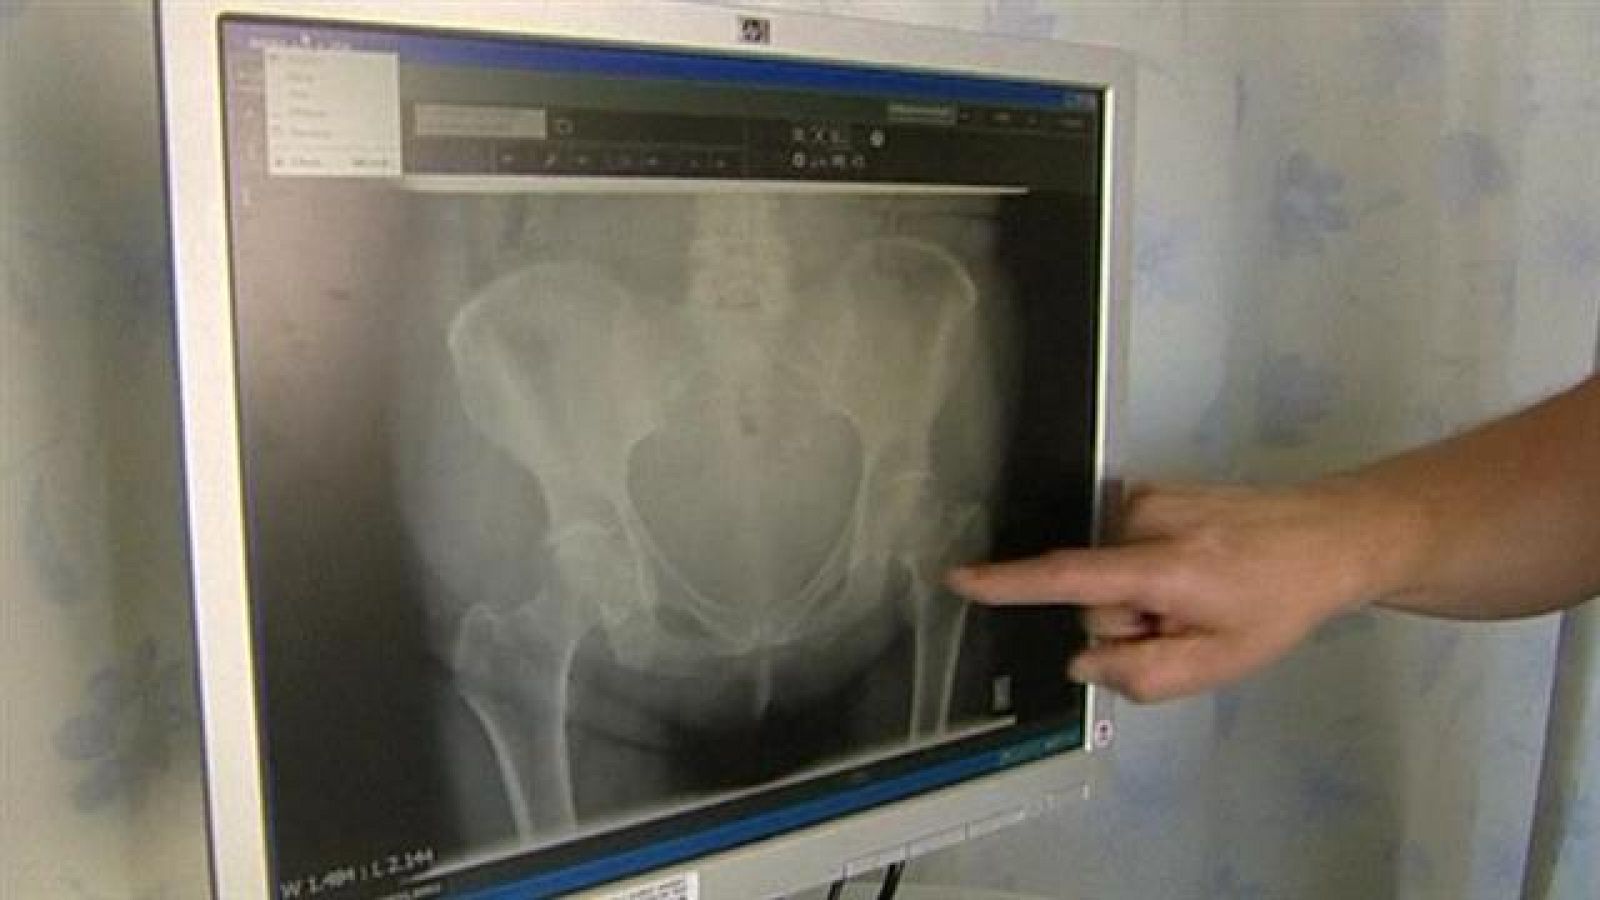

Al menos 300 canarios podrían estar entre los afectados por las prótesis de cadera defectuosas. El abogado de medio centenar de pacientes asegura que tienen nuevas pruebas contra las compañías fabricantes. Con la batalla judicial en marcha, todavía muchos siguen esperando a que se les cambie el implante.